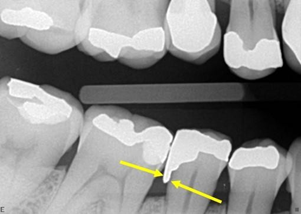

Figure 1 Interproximal radiography of the Molares D region, diagnosed on panoramic radiography. The arrow points to the distal of tooth 16, showing excess of the prosthetic crown, that causes iatrogeny.

Figure 2Periapical radiography of the lower molars D region, diagnosed on panoramic radiography. The yellow arrows point to the distal of tooth 45 and mesial of tooth 47, showing a gross excess of amalgam restorations, which characterize iatrogeny. The red arrows point to the resorption of the alveolar bone crest, due to iatrogenesis. Note that tooth 46 is absent, with teeth 45 and 47 tilted in that space.